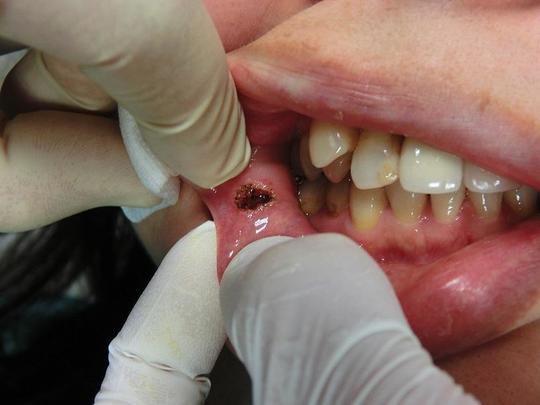

口腔内のイボ・できもの(線維腫・乳頭腫などの良性腫瘍)をCO2レーザー(炭酸ガスレーザー)で切除した症例。

線維腫、乳頭腫などは誤って粘膜を噛んでしまうと出現することが多く、またその部位を繰り返し噛んでしまい大きくなるケースもあります。

口唇の場合

術後

術後は口内炎のようになりますが、ほとんど痛みやしみたりしません。口内炎のような跡も1週間程度で小さくなってきます。

頬粘膜(口唇に近い頬粘膜)の場合

術直後

術後1週間